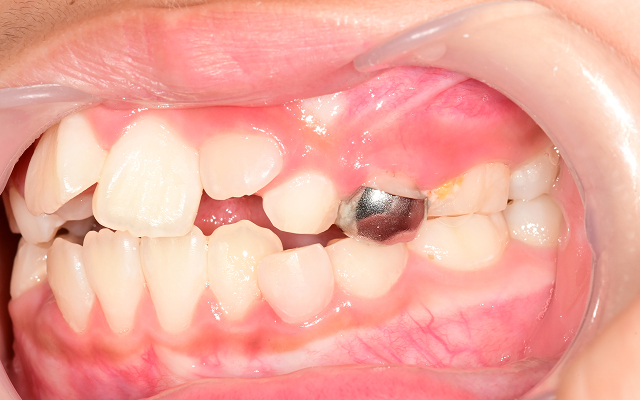

• 02

영구치가 덧니로 나거나 발치가 필요한 경우로 악화(발치교정)